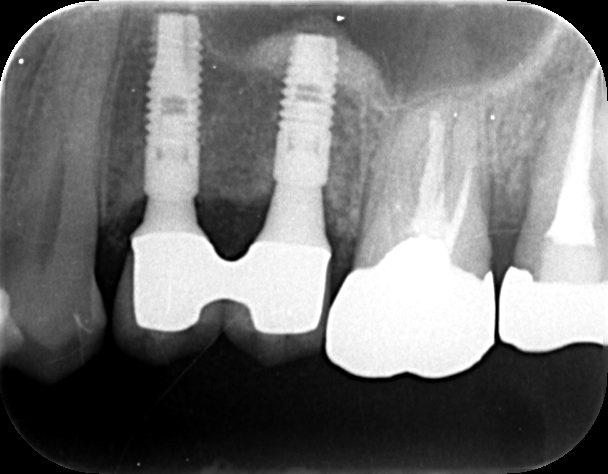

2025年

メインテナンス時 変わらず安定している。 -

開業間もない頃に来院され、あれから19年が経ちました。インプラントを埋入してから15年が経ち、現在もメインテナンスで通院していただいています。開業してからもう何百本もインプラントの手術をしてきましたが、長期予後を見ていると、残念ながらインプラントがだめになってしまった患者さんもみえます。同じように手術をしているのに、駄目になってしまう方と何年も変わらず維持されている方との差は何かと考えます。①まず何よりもその方の持っている免疫力。歯周病菌に対してどれだけ抵抗力があるか。体や骨の強度。②その次にその方のかみ合わせ。ギシギシ歯軋りしたときに犬歯だけで下顎が誘導され、臼歯部が離開して過度な負担がかからない。③そして歯磨きをある程度しっかりしているかどうか。他にも多くの要因はあると思いますが、これら3つが揃っているとインプラントが駄目になる可能性は低くなると考えています。そのため当院では基本的には犬歯の位置がいい方、よくなければ矯正治療により咬合を改善した方で、歯磨きをある程度しっかりと出来る方にインプラントを行うようにしています。歯がなくなってしまった原因を解決せずに歯がなくなってしまったから単純にインプラントをお勧めすることはありません。